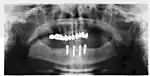

Panorex radiograph showing implants

Xray of four Straumann implants and abutments

When a removable denture is worn, retainers to hold the denture in place can be either custom made or "off-the-shelf" (stock) abutments. When custom retainers are used, four or more implant fixtures are placed and an impression of the implants is taken and a dental lab creates a custom metal bar with attachments to hold the denture in place. Significant retention can be created with multiple attachments and the use of semi-precision attachments (such as a small diameter pin that pushes through the denture and into the bar) which allows for little or no movement in the denture, but it remains removable.[17]:33–34 However, the same four implants angled in such a way to distribute occlusal forces may be able to safely hold a fixed denture in place with comparable costs and number of procedures giving the denture wearer a fixed solution.[54]

Alternatively, stock abutments are used to retain dentures using a male-adapter attached to the implant and a female adapter in the denture. Two common types of adapters are the ball-and-socket style retainer and the button-style adapter. These types of stock abutments allow movement of the denture, but enough retention to improve the quality of life for denture wearers, compared to conventional dentures.[55] Regardless of the type of adapter, the female portion of the adapter that is housed in the denture will require periodic replacement, however the number and adapter type does not seem to affect patient satisfaction with the prosthetic for various removable alternatives.[56]